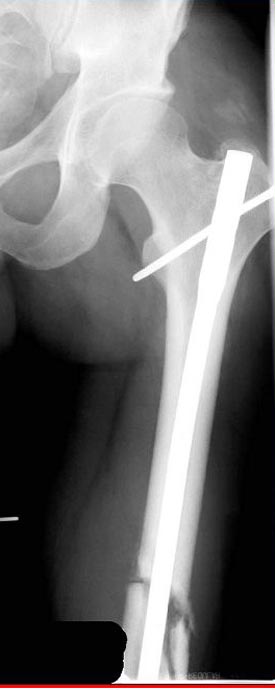

Коллеги,Комментарии к случаю лечения ложного сустава бедра аппаратом типа Илизарова, показанному здесь

Лечение бедра - ургентное оперативное лечение антеградным с минимально рассверливанием, фиксацией с минимальным диаметром штифта и плюс irrigation and debridment и с закрытием поперечной до 10 см раны на уровне перелома в день поступления.

Снимки представлены: 1 мес; 3 мес; 1 год; 2 года, предоперационные и ротационная КТ грамма

Деформация:

Вальгус- 17 градусов

Рекурватум 5 градусов

Укорочение 2.5см

Ротационно 22 градусов внутренная

Смещение диафиза по поперечнику 75%